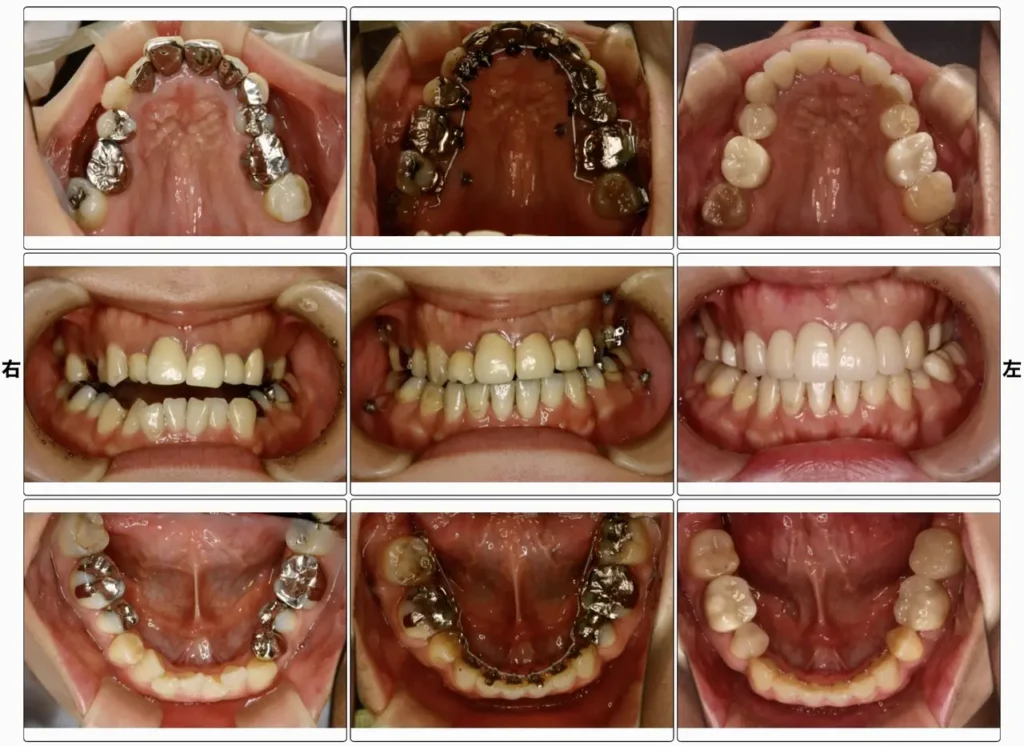

症例1 開咬

「奥歯でしか咬めない、食事がしにくい」

舌側矯正治療(装置名:インコグニート)150万円 月1回の調整(7,000円)

舌側矯正(歯の内側矯正)で対応、噛み合わせだけでなく歯並びも良くなり、銀歯も被せ直しました。

治療期間2年。

開咬は、咬み合わせが開いて一部でしか歯が咬んでない状態で、前歯が開いている症例が多いです。原因は、舌突出癖(前歯で舌を挟んで飲み込む)が多いです。舌突出癖があると様々なお口の機能障害が出やすく、かみ合わせや歯並び、呼吸、嚥下に問題が出ます。矯正治療中、治療後も正しい舌の位置の獲得訓練、お口周辺の筋機能訓練(MFT)なども一緒にやらないと治療もうまくいきませんし、治療後もまた開いてしまいます。難しい治療です。

舌側矯正は、歯の裏側に装置をつけて行う矯正で、治療中の見た目の良さが最大の利点です。欠点は、裏側なので頑張ってお手入れをしなくてはいけません。治療ゴールは、表側からでも裏側からでも同じです。治療のスピードも変わりませんが、コンピュータ上で装置を設計、ワイヤーもロボットが曲げてくる完全オーダーメイドなので正確さは高いかもしれません。